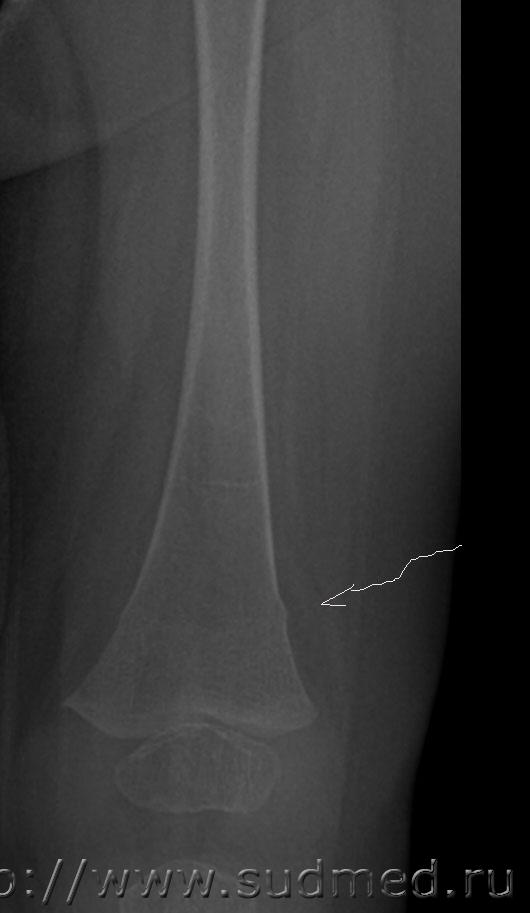

Добрый день, уважаемые коллеги. Нужна помощь в оценке степени тяжести поднадкостничного перелома нижней трети диафиза бедренной кости у ребенка 1 года. Судя по снимкам, перелом вколоченный. По версии следствия, перелом образовался во время массажа, ребенок лежал на животе, со слов массажиста в момент упора ребенка стопами в ладонь врача, при движении вперед в горизонтальном положении ребенок заплакал. В вертикальном положении при упоре стопами в пеленальный стол стал приподнимать больную ногу и плакать. снимки выполнены в тот же день. Рентгенолог изменений структуры кости на снимке не отмечает.

Я рентгенолог не профессиональный и не детский, но перелома не вижу. Ограниченное тяжистое или симметрично-очаговое вспучивание компакты (отторжение надкостницы?) в супракондилярных зонах - местах крепления мышц голени.

Перелом есть. По типу "зеленой веточки", судя по симметричности, действительно вколоченный.

Да. По формальному признаку: перелом диафиза бедренной кости. Легкий или средний вред Мед.критериями всерьез не обосновать.

Честно говоря, какого -либо уплотнения губчатого вещества я тоже не вижу, возможно Вы правы по поводу отторжения надкостницы. Но две консультации рентгенологов указывают на перелом. Думаю нужна консультация снимков детским травматологом-ортопедом с привлечением рентгенолога.

Противоречивые сведения. Если разные рентгенологи видят разное, то вы правы - нужна ещё консультация.

Впрочем, в нижней трети правого бедра край тени кости тоже не вполне идеально ровный.

Кроме того, даже если допустить, что сил у массажистки предостаточно для причинения вколоченного перелома бедра, то, как я предполагал бы, он должен сопровождаться более грубыми повреждениями мягких тканей.

Вы правы, максимально привлекайте консультантов. Перелом при указанных обстоятельствах может быть только патологическим.